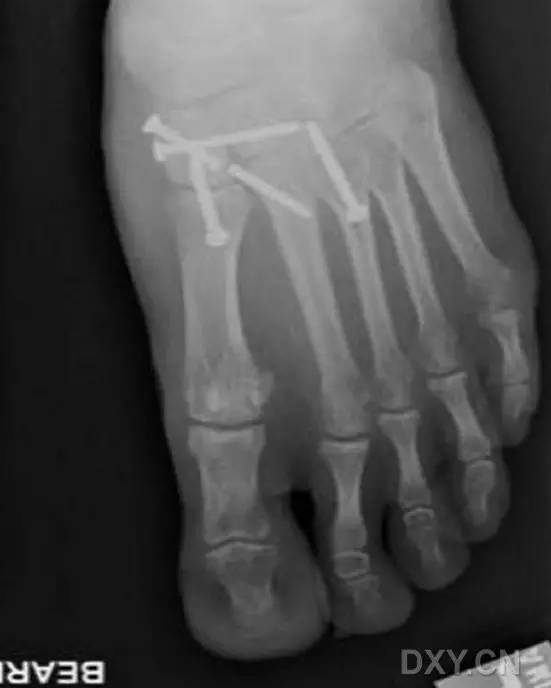

最后,处理第 1 跖楔关节不稳等其他损伤情况。对于其他损伤可采用关节外固定技术进行处理(图 5),相关技术细节,可参考其他相关文献,在此不再赘述。

图 5. 术前 X 线片和透视观察显示,第 2 跖骨基底骨折伴第 1 跖楔关节不稳(A、B)

采用本文介绍的 Lisfranc 螺钉固定技术和关节外内固定技术进行损伤进行固定治疗。术后 3 年随访表明,原损伤部位复位、固定位置良佳,几乎无明显皮肤瘢痕(D),足趾稳定性良好 (E)。